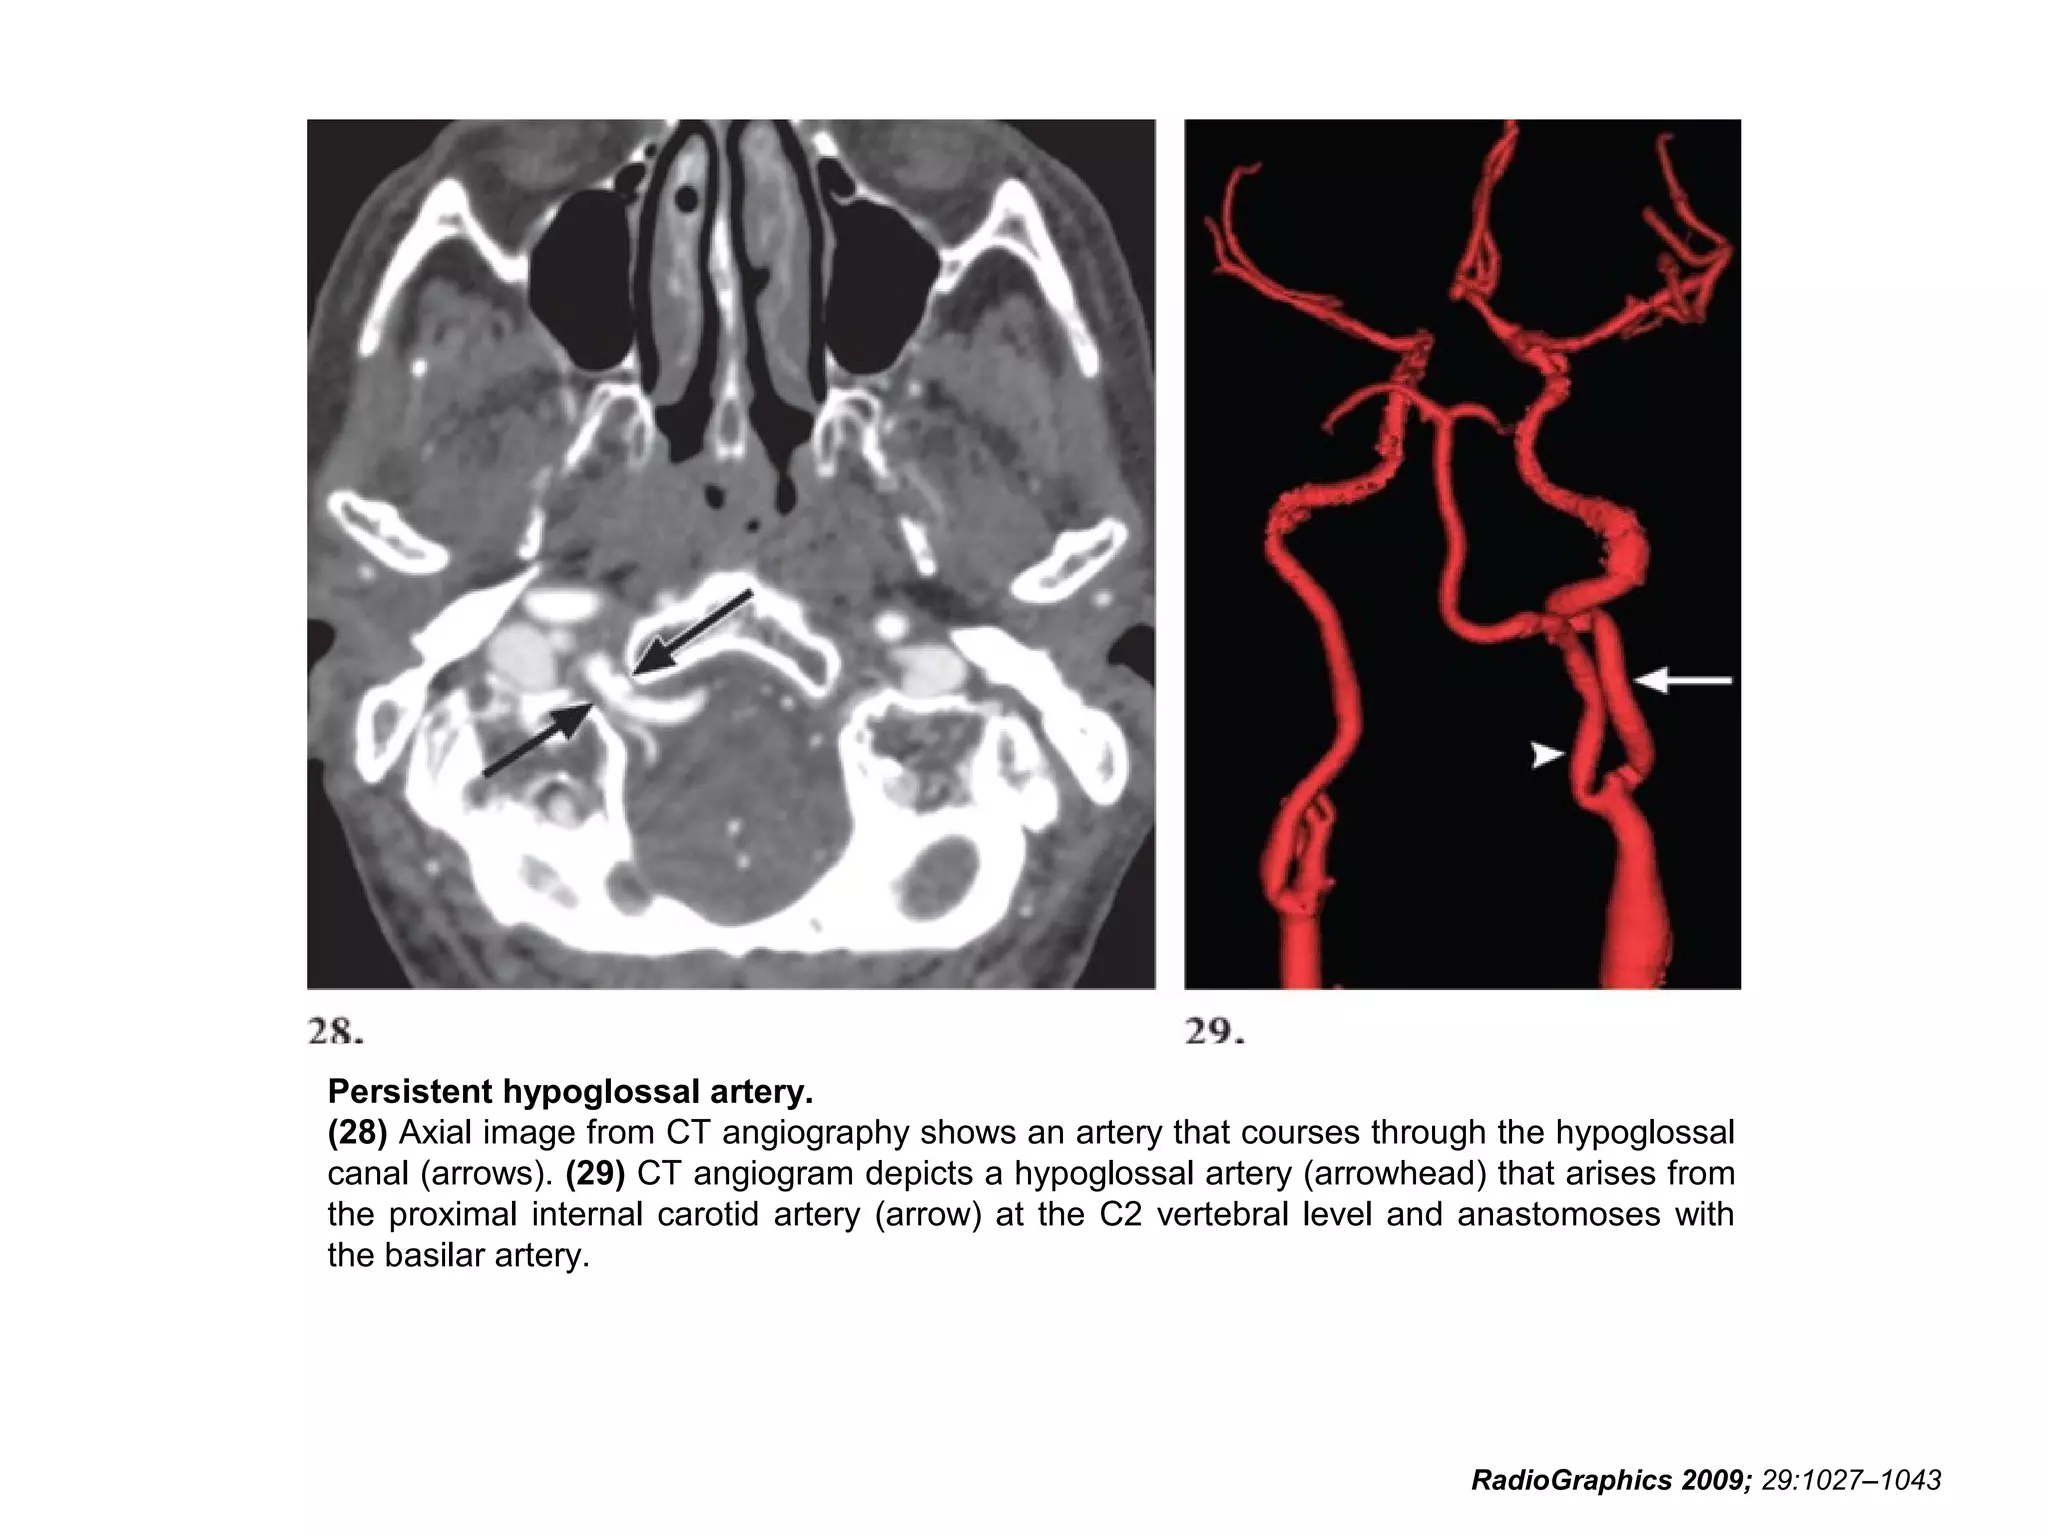

Persistent hypoglossal artery.

(28) Axial image from CT angiography shows an artery that courses through the hypoglossal

canal (arrows). (29) CT angiogram depicts a hypoglossal artery (arrowhead) that arises from

the proximal internal carotid artery (arrow) at the C2 vertebral level and anastomoses with

the basilar artery.

RadioGraphics 2009; 29:1027–1043

• 76.

Persistent hypoglossal artery. (28)Axial image from CT angiography shows an artery that courses through the hypoglossal canal (arrows). (29) CT angiogram depicts a hypoglossal artery (arrowhead) that arises from the proximal internal carotid artery (arrow) at the C2 vertebral level and anastomoses with the basilar artery. RadioGraphics 2009; 29:1027–1043